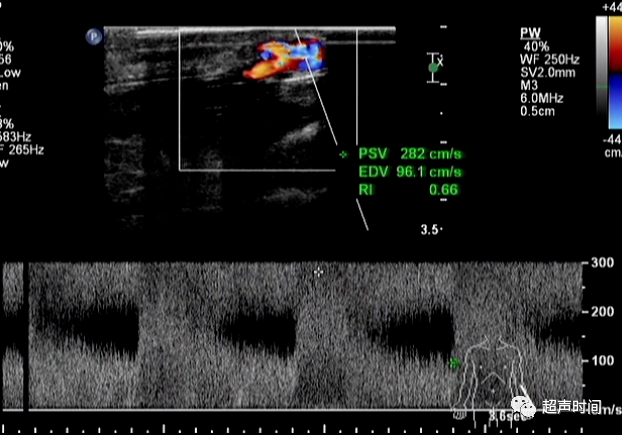

高速低阻血流频谱。如图 3 所示。

图 3 造瘘后流入动脉频谱。 流入动脉流速增高、阻力减低